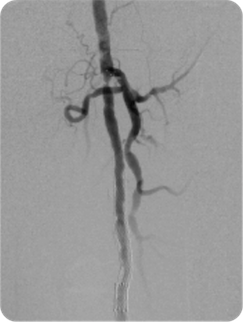

腎障害のある方への炭酸ガス造影に関して

カテーテル検査、治療には、通常造影剤という薬剤を血管に注入する必要があります。

しかし造影剤には腎臓に対する毒性やアレルギー反応という問題があり、重篤な腎機能障害を有していたり、過去に造影剤にて重篤なアレルギー症状を来したことのある患者さんには使用が困難です。

そこで当院では、こういった患者さんに対してのみ、生体に影響が少ないとされる炭酸ガスを造影剤の代わりに用いています。

炭酸ガスは酸素に比して約20倍も血液に溶け、そのほとんどが投与後すぐに体外に排出されます。

低侵襲性、低コスト、そして何よりも無腎毒性、無アレルギー性を最大の利点としています。

通常の造影剤より画像の鮮明さという点で劣り、完全に通常の造影剤に取って代わることはできませんが、炭酸ガスを用いることによって通常の造影剤の量を減量することも可能です。 また炭酸ガス造影に血管内超音波検査などの血管内イメージ機器を併用することにより更に造影剤の低減が可能です。

冠動脈や脳動脈など、短期的な虚血でも強い症状が出現する臓器への使用は困難ですが、主に下肢などの下半身の血管造影の際に施行しています。

炭酸ガスによる大腿動脈の造影

通常の造影剤による大腿動脈の造影